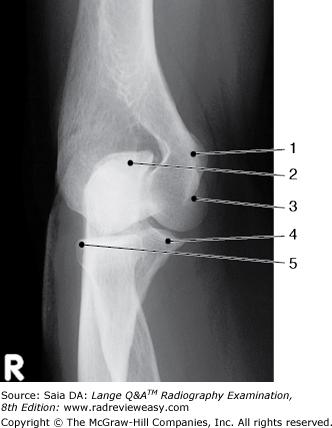

Identify the structure labeled 1 in the AP projection of the knee shown in Figure 2–16.

A Lateral condyle B Lateral epicondyle C Medial condyle D Medial epicondyle

Medial epicondyle